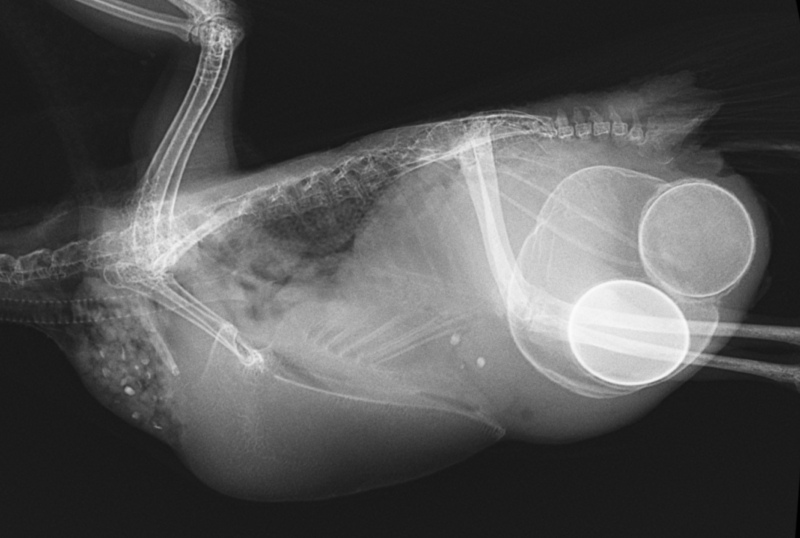

考えられる病気:慢性発情、卵づまり(卵塞症)、卵管蓄卵材症、腹壁ヘルニア、腫瘍など

考えられる原因/病気:オカメパニック、換羽、骨折、脱臼、腫瘍、毛引き症、自咬症など